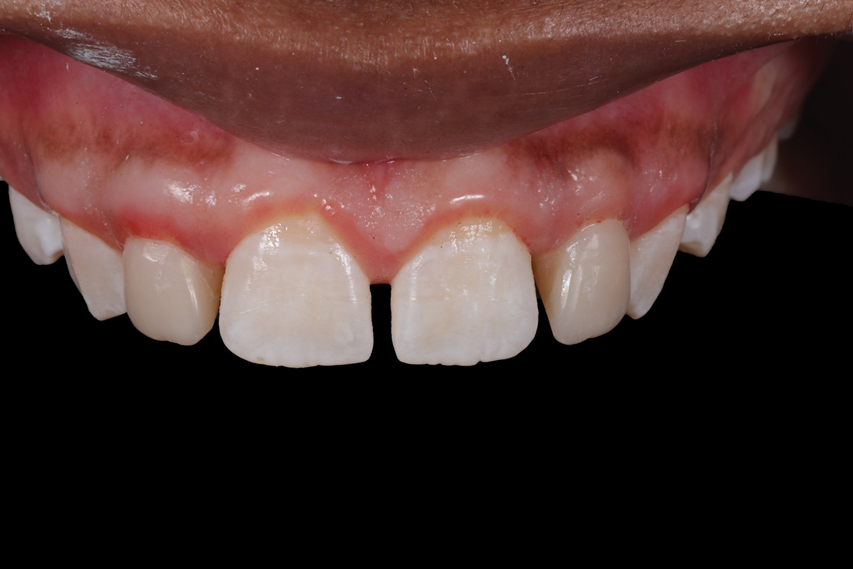

The rubber dam was removed from the mouth, and the excess material was removed with a No. 12B scalpel blade and a fine diamond bur. Next, the light-reflecting and light-deflecting zones were verified with a pencil and adjusted with finishing burs.11 The occlusion was then verified statically and dynamically using articulating paper and adjusted as needed. After finishing, the immediate postoperative polishing process was accomplished with a series of polishing discs followed by the use of a buffing disc with a diamond polishing paste (Figure 30). Eight days later, the patient returned to the office, and the final polishing was accomplished with polishing discs and diamond polishing paste (Figure 31 through Figure 35).

An assessment of the shape and shade of the final restorations was performed. It was noted that the incisal edges of the restored lateral incisors were not as white as those of the central incisors. Rather than adding additional stain to the lateral incisors, the patient expressed her desire to have some of the white staining removed from the central incisors using a resin infiltration technique after her orthodontic treatment. The final orthodontic treatment for the maxillary arch would involve closing the spaces in the anterior area, protracting the posterior teeth, and finishing in a Class II relationship. For the mandibular arch, the goal would only be to maintain the current positions of the teeth.

(31.) Retracted maxillary view of the completed restorations after final polishing.

Figure 31

(32.) Posttreatment smile, left lateral smile, and right lateral smile photographs, respectively.

Figure 32

(33.) Posttreatment smile, left lateral smile, and right lateral smile photographs, respectively.

Figure 33

(34.) Posttreatment smile, left lateral smile, and right lateral smile photographs, respectively.

Figure 34

(35.) Posttreatment retracted occlusal view of the final restorations.

Figure 35